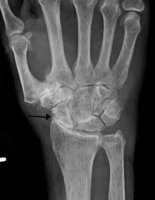

Reumatyzm groźną chorobą cywilizacyjną

Bóle stawów są problemem, z którym zmaga się wiele osób. Według statystyk są one najczęstszą przyczyną zgłaszania się chorych do lekarza. Dotykają zarówno młodych, jak i osoby w podeszłym wieku. Czy bóle stawowe mogą być objawem poważniejszej choroby?